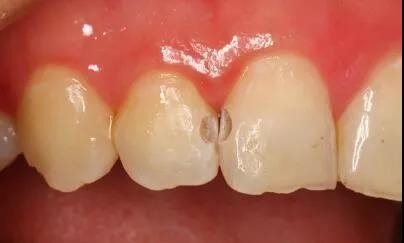

牙齿邻接处变色

这些酸对牙齿外层的牙釉质具有酸蚀作用,由此牙齿开始变色,时间一长甚至会形成蛀牙龋洞。

至于邻面龋,顾名思义,它是发生在牙齿与牙齿对接的相邻面,也就是牙缝中,由于它是在“夹缝中生存”,潜伏性很强,所以没有发展到比较严重的时候是难以发现的。